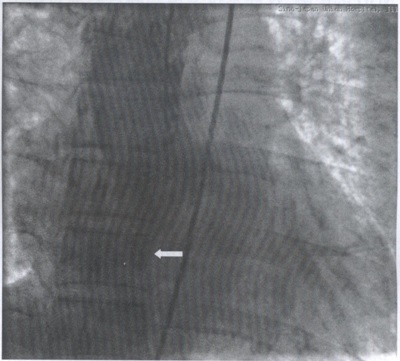

诊断:主动脉右冠窦瘤破裂入右心房。后经主动脉根部造影证实上述诊断(图2),并按照室间隔缺损介入封堵术的治疗方法,成功封堵主动脉窦瘤破裂口。患者即刻胸闷、心悸消失。心电图示:下移ST段恢复至正常,心率降至75次/min(图3)。

图2 正位主动脉根部造影示造影剂经主动脉右窦入右心房(箭头所示)